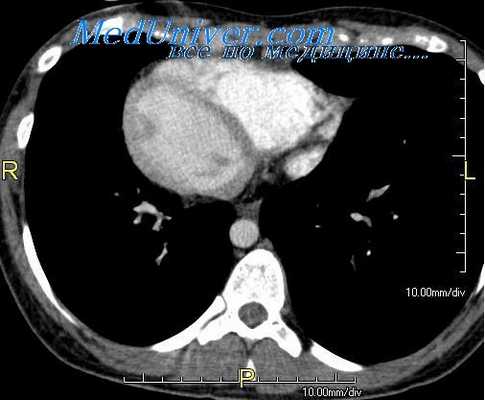

Локализация желудочков сердца устанавливается по морфологии комплекса QRS в грудных отведениях; над анатомически ПЖ обычно регистрируются комплексы rS или RS, над анатомически ЛЖ — желудочковые комплексы в виде qRs, qRS или qR. При ангиокардиографическом исследовании, в частности при вентрикулографии, уточняют внутреннюю архитектонику желудочков и характер протекающей крови. При неясных вентрикулограммах расположение желудочков и их анатомия могут быть установлены косвенно, а именно по характеру положения магистральных сосудов.

Например, в правосформированном сердце нормальная локализация магистральных сосудов и полная или простая их транспозиция будут свидетельствовать и о нормальном положении желудочков, а крайне левая и передняя позиция восходящего отдела аорты по отношению к медиально и сзади расположенному легочному стволу (ЛС), за редким исключением, отмечается при инверсии желудочков (нормальное их развитие), т. е. аорта будет отходить от артёриальпого, анатомически ПЖ, а ЛС — от венозного, анатомически ЛЖ. Аналогичная ситуация, но с учетом зеркальности изображения отмечается и в левосформированных сердцах.

Взаимоотношения аорты и легочного ствола ориентировочно определяются рентгенологическим исследованием и точно — ангиокардиографией.